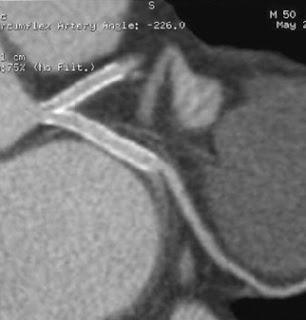

Contrôle systématique d'une angioplatie à 6 mois du tronc commun: resténose non significative (hypodensité intrastent) du stent commun IVA et du stent de la circonflexe proximale. In Annales de Cardiologie et d'Angéiologie Volume 56, Issue 7,December 2008, Pages 359-354